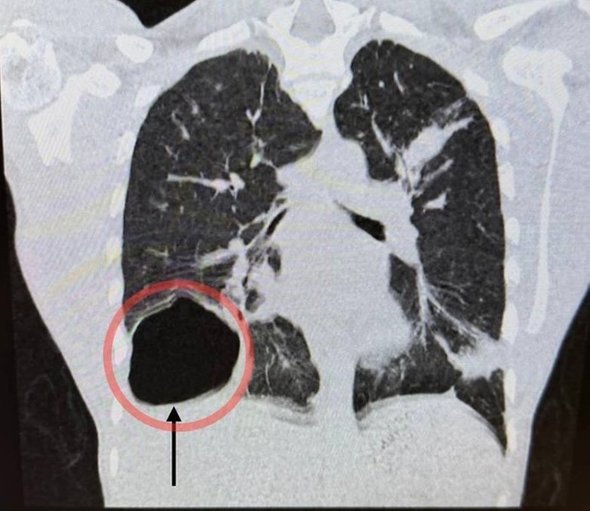

В клинику 17-летний молодой человек обратился с жалобами на слабость, высокую температуру, кашель и боль в правой половине грудной клетки. После проведенной диагностики врачи выявили у пациента крупную паразитарную кисту правого легкого. Ее размер был сопоставим с размером головы новорожденного ребенка. Киста образовалась из-за попадания в организм гельминтов — эхинококков.

«После подтверждения диагноза с помощью лабораторного контроля и компьютерной томографии мы приняли решение о проведении операции. В нашем отделении накоплен большой опыт хирургического лечения данной патологии малоинвазивными методами через несколько проколов. Такая щадящая операция сильно сокращает травматичность вмешательства и сроки реабилитации. В данном случае мы избежали широкого разреза. Операция прошла успешно, послеоперационный период протекал без особенностей», — рассказал об этом случае завотделением детской хирургии Владимир Трунов.

фото: vk.com/mocomd